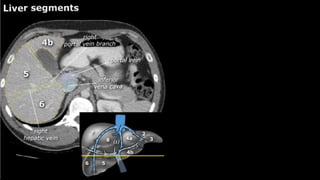

•Liver • A normalliver enhances homogeneously (irrespective of the scan phase). The liver receives about 80% of its blood through the portal vein (= nutrient-rich blood from the intestines). The remaining 20% is supplied by the hepatic artery. y is present, it is important to document its location. This may be crucial to any surgical options. Using the Couinaud classification, the liver is subdivided into eight individually functioning segments. Each segment has its own afferent hepatic artery and portal vein, and efferent hepatic vein and efferent bile ducts